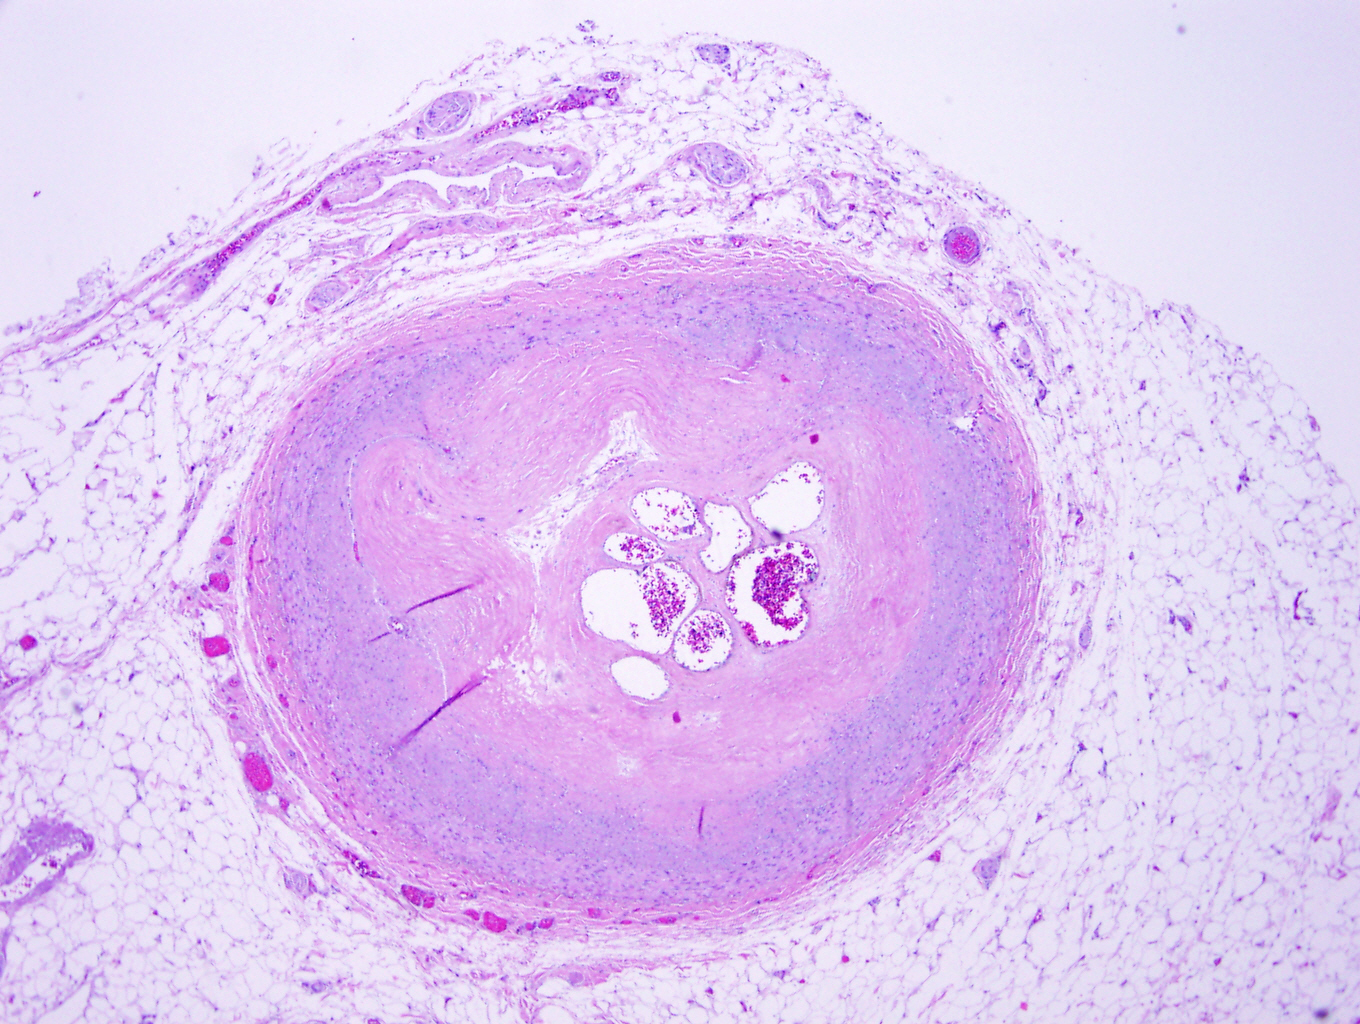

Microscopic (histologic) description

- Fatty streak: subendothelial accumulation of foam cells without necrotic core or fibrous cap

- Fibrous cap atheroma (Am J Med 2009;122:S3):

- Well formed necrotic core with overlying fibrous cap; smooth muscle cells, macrophages, lymphocytes and connective tissue components may be present

- With rupture: luminal thrombus communicates with underlying necrotic core

- With erosion: luminal thrombosis; no communication of thrombosis with necrotic core

- Fibrocalcific plaque: collagen rich plaque, contains large areas of calcification with few inflammatory cells, necrotic core may be present

Microscopic (histologic) images